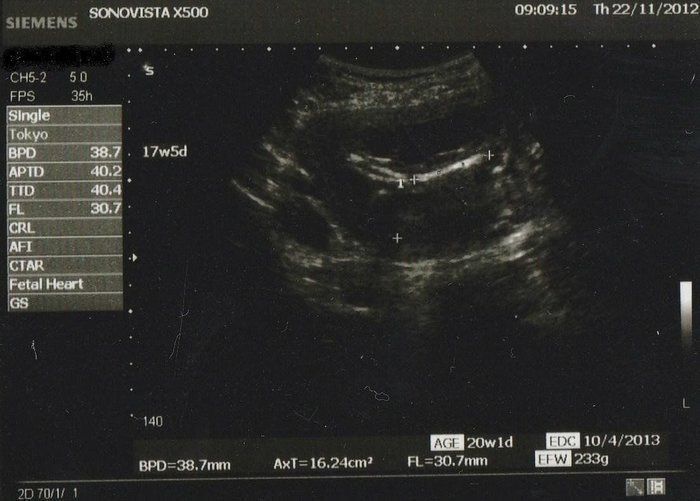

Amiさんの妊娠17週目のエコー写真

約30mmの大腿骨の写真です。推定体重233g! 一度大きくなったおなかだからか、おなかが目立ち始めるのがとっても早く、もう立派な妊婦体型! おなかの写真を撮るときは、長女もちゃっかり自分のおなかをだして一緒に写真を撮っていました。